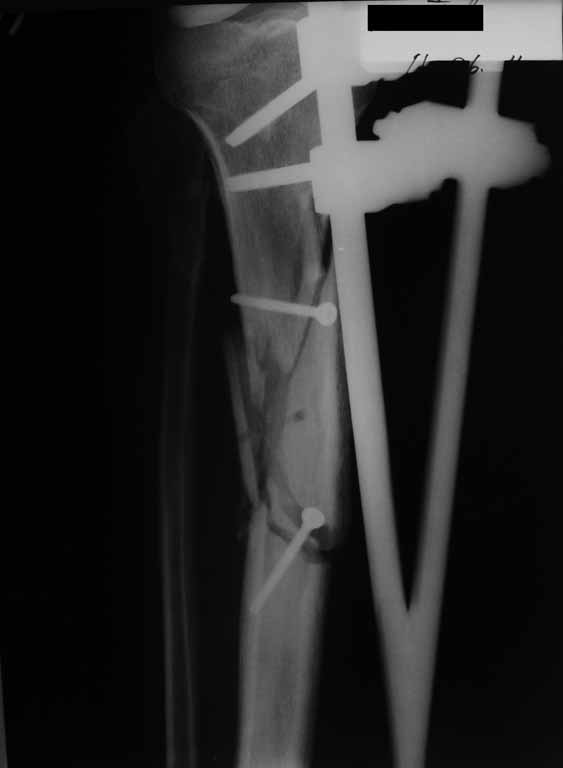

Привожу пример: Пациент с открытой тяжелой ЧМТ.

Диагноз при поступлении: Открытый оскольчатый перелом свода и основания черепа,субдуральная гематома, ушиб головного мозга тяжелой степени. Открытый оскольчатый перелом костей правой голени. Шок 3 Кома 3

По тяжести ЧМТ ( по данным РКТ) выжить был не должен в принципе.

При поступлении оперирован : трепанация, ПХО, остеосинтез голени.

Консолидация в аппарате внешней фиксации к 2 месяцам. Аппарат снят через 2,5 месяца.

Фото в приложении.